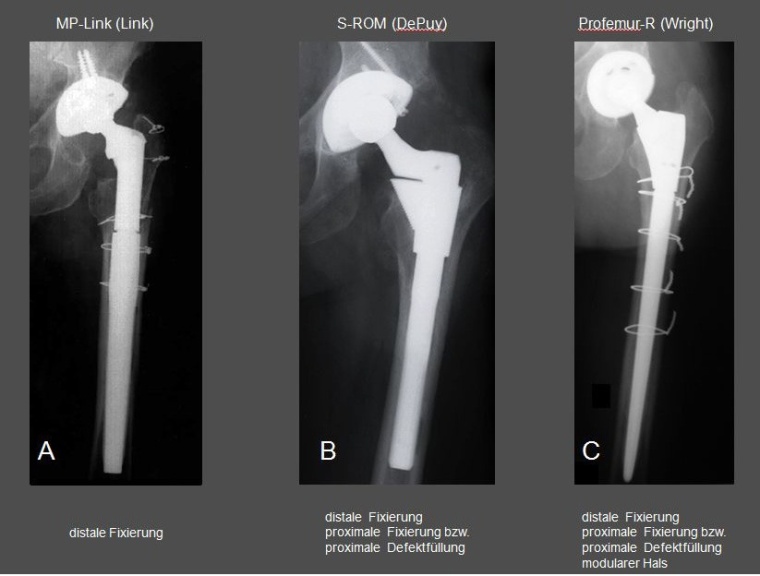

Gemäß DIMDI (2013) gilt als zu kodierende modulare Endoprothese (5-829.k) eine gelenkbildende Implantatkomponente, die aus mindestens 3 metallischen Einzelbauteilen besteht, welche in ihrer Kombination die mechanische Bauteilsicherheit der gesamten Prothese gewährleisten. Der Aufsteckkopf der Endoprothese wird dabei nicht mitgezählt (Abb. 2).

Grundsätzlich lassen sich drei verschiedene modulare Schaftkomponenten definieren:

A. Schaftimplantate mit rein distaler Fixierung

B. Schaftimplantate mit distaler und proximaler Fixierungsoption bzw. proximaler Defektfüllung

C. Schaftimplantate mit distaler und proximaler Fixierungsoption bzw. proximaler Defektfüllung sowie modularem Hals

Unter allen drei Implantattypen gibt es Modelle mit Verlängerungskomponenten bzw. Verriegelungs- bzw. Verbolzungsmöglichkeit (Abb. 3).